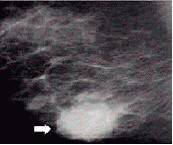

유방촬영술(mammography)은 유방암 진단에 필수적인 검사로, 촉진과 초음파검사 등에서는 발견이 어려운 미세석회화(microcalcification)와 같은 유방촬영술에서만 관찰 가능한 따위 조기암 병변을 찾는 데 중요한 역할을 합니다(미세석회화란 유방 조직에 칼슘 성분이 쌓여 엑스선 영상에 작고 하얀 부분으로 나타나는 것인데, 그 일부는 암의 초기 증상일 수 있습니다). 90~95%의 정확성을 보이면서 크기 5mm 안팎의 작은 종괴(덩이)를 아주 민감하게 찾아내는, 유방암 조기 진단에 이상적인 검사입니다. 하지만 우리나라의 젊은 여성은 유방에 섬유질이 많아 유방촬영술만으로는 정확한 진단을 내리기가 어렵습니다. 유방이 고밀도일수록 유방촬영술의 민감도가 낮아지기 때문입니다. 이런 경우엔 초음파검사를 병행합니다.